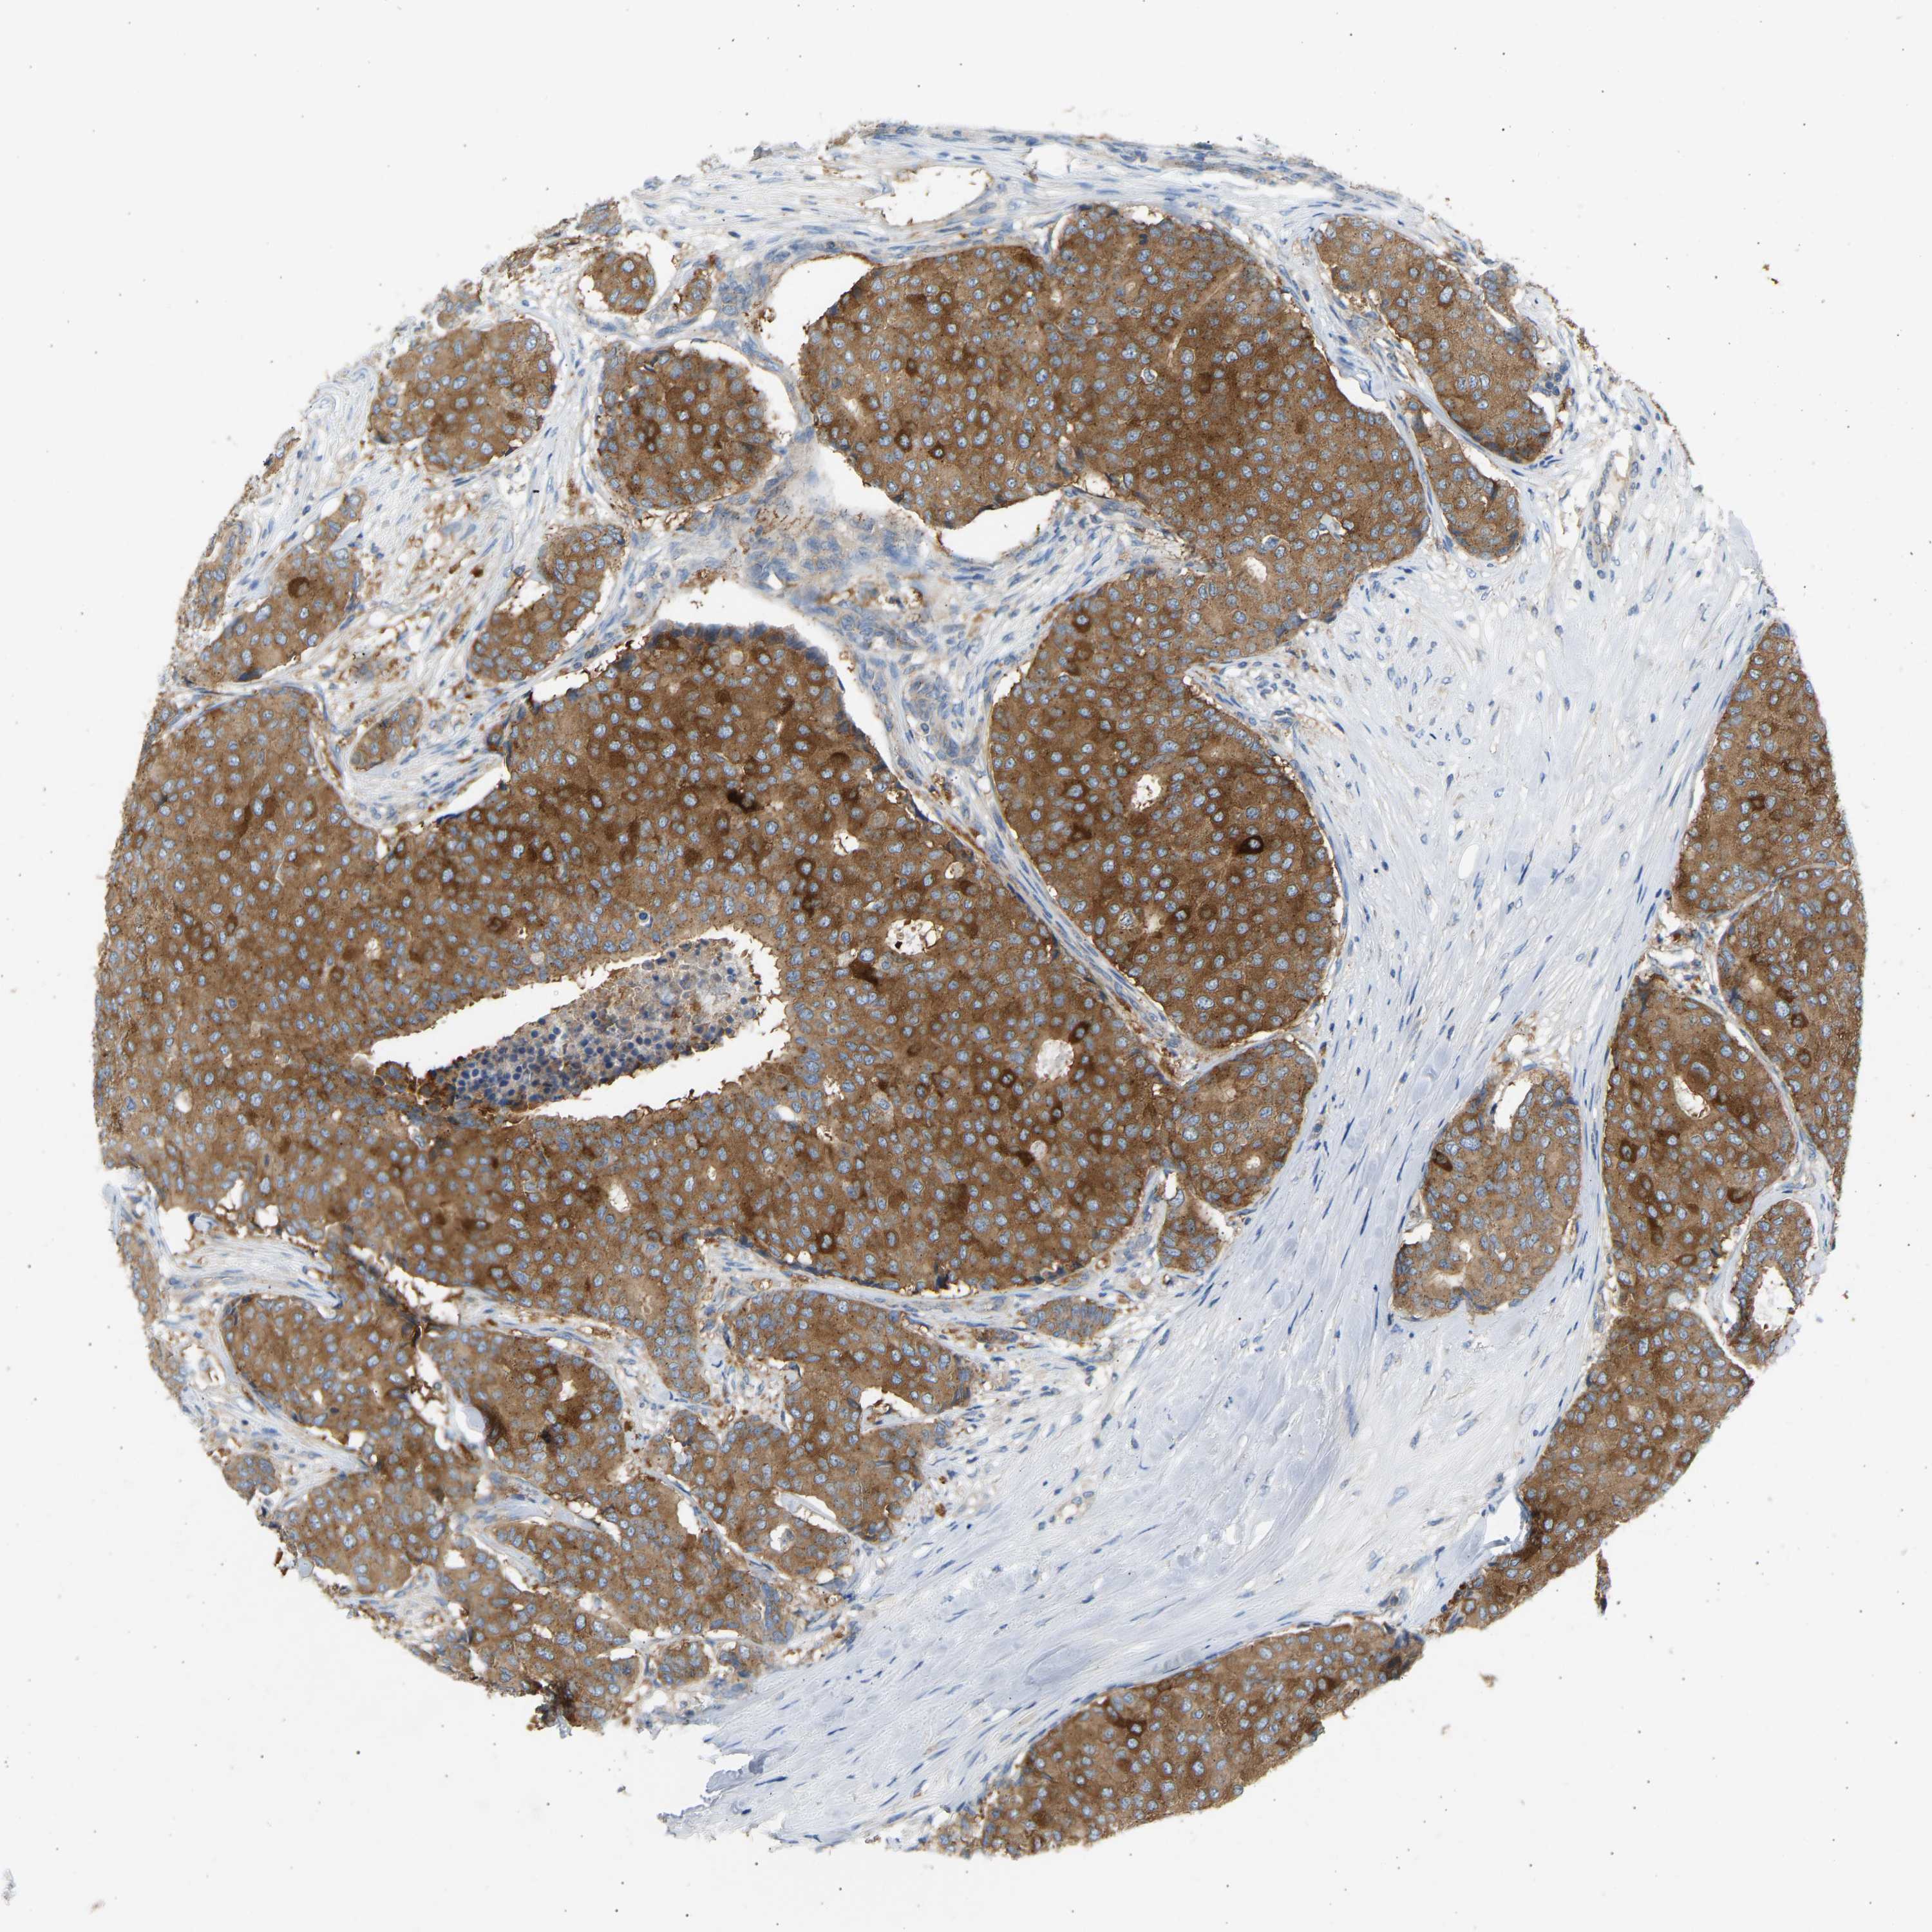

CANCER BREAST CANCER Show tissue menu

BRCA TCGA BRCA VALIDATION PROTEIN EXPRESSION

ANTIBODIES

AND

VALIDATION